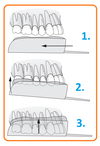

Care sunt tehnicile de baza de retractie gingivala pentru amprenarea dentara in protezarea fixa cu ata de retractie?

Utilizarea unei ate:

- Se asteapta citeva minute pentru retractie

- Se extrage si se face amprenta in <30’’:

- Timpul in care gingia revine la loc

Utilizarea atei duble:

- Prima ata: compresie

- Subtire (000) si se introduce fara overlap la fund

- Se lasa in timpul amprentarii:

- Elimina lichidul crevicular

- Evita singerarea

- A doua ata: retractia orizontala

- Mai groasa (0→3) si se introduce deasupra

- Se scoate inaintea amprentarii

- Prima ata: compresie